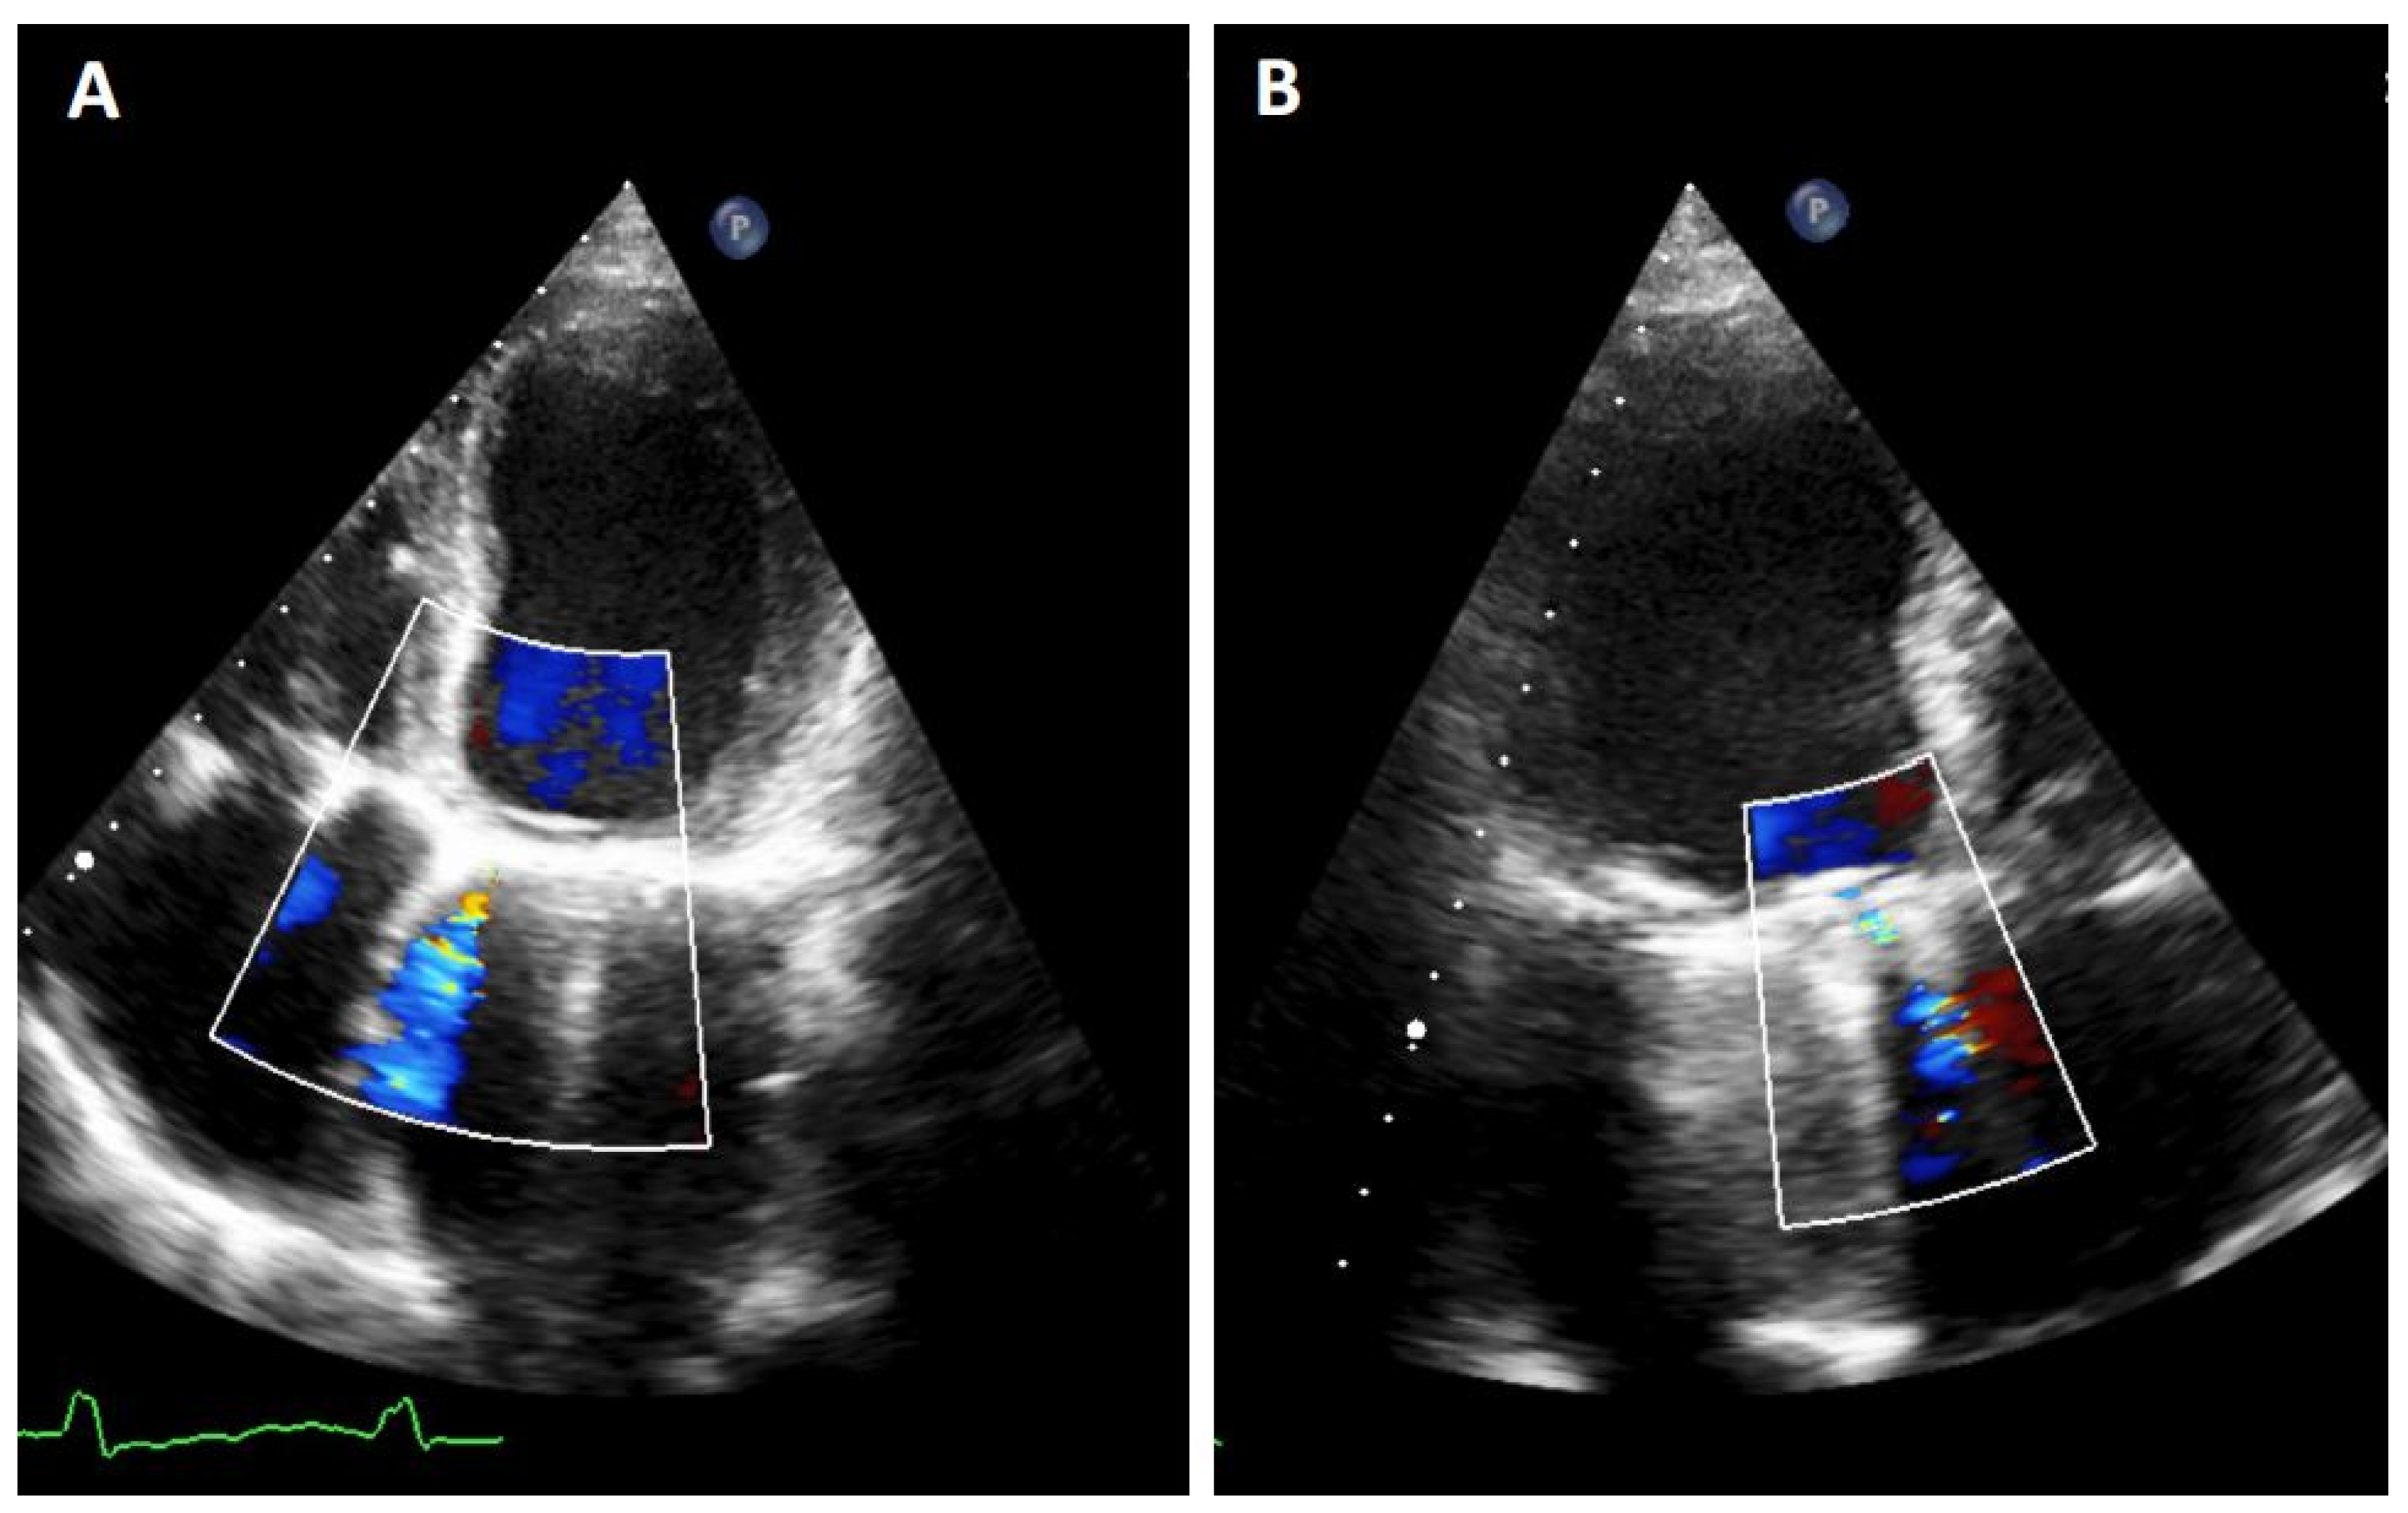

3.2. TEE